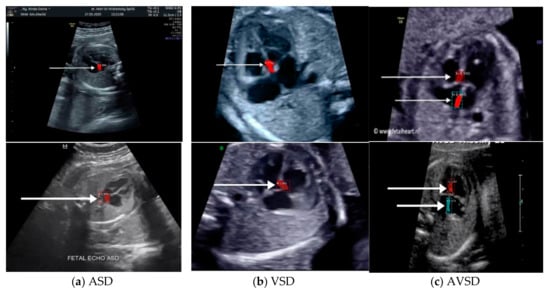

Images with inappropriate anatomical planes (cropped or badly captured) and those with calipers were excluded. The dataset composition was clearly imbalanced (some classes were more frequent than others), as is usually the case in real clinical scenarios. The sample of the raw ultrasound image was based on four views in normal anatomy, as depicted in Figure 2. In such sample, there are the left atrium (LA), left ventricle (LV), right atrium (RA), right ventricle (RV), ductus arteriosus (DUCT), superior vena cava (SVC), aorta ascendens (AoA), aorta descendens (Ao), and main pulmonary artery (MPA), whereas the sample of the raw ultrasound image of abnormal anatomy structure, with the three heart defects such as ASD, VSD, and AVSD condition, is compared to normal anatomy structure in Figure 3. In the abnormal structure, there are hole (H) as heart defect in each condition. Each defect has the variation of hole size; such hole size indicates the disease severity. However, in this study, we only detected the hole, without measuring the hole size.

Figure 3.

Fetal heart scan in 4CH view for CHDs detection: (a) ASD; (b) VSD; (c) AVSD; and (d) Normal.